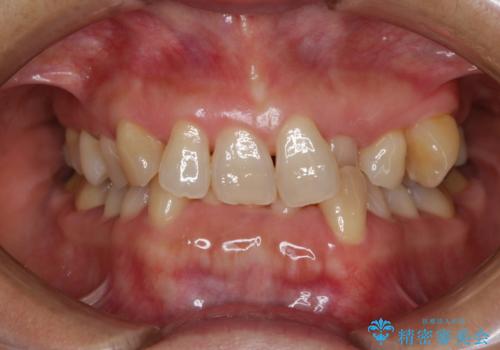

- 20代女性

抜歯をして第1小臼歯分のスペースを獲得することにより、ガタつきの改善と前歯のリトラクトをおこない、横顔の印象もすっきりとし、整ったEラインを作ることができました。